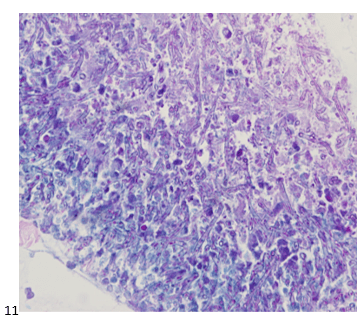

A 58-year-old male presented with multiple lung nodules and a brain mass. We reviewed the brain mass excision from an outside institution and agreed with the original diagnosis of anaplastic oligodendroglioma, WHO grade III with a Ki-67 proliferation index that approached 20%. EGFR was not amplified (ratio 1.2), but 1p/q19 co-deletions were noted in greater than 75% of tumor cells. To rule out primary versus metastatic disease, the patient had a CT scan-guided biopsy of right upper lobe lung mass. No malignant cells were identified in the sample; however, necrotic debris and abundant fungal hyphae were noted (Images 7-9). A portion of the sample was sent to Microbiology for culture. The following day, a GMS and PAS stains were performed on paraffin-embedded sections of the cell block which demonstrated the same fungal hyphae seen in the smears and cell block preparations (Images 10 & 11).

Diagnosis: Abundant fungal hyphae, consistent with Aspergillus